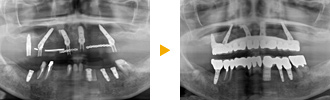

大阪府豊中市60代男性の症例。

歯周病で上の歯を多く失っておられ、残っている歯もグラグラな状態だったため、抜歯してオールオン6で全体的に治療しました。

上顎をオールオンフォーで治療する計画をたて、インプラントを6本埋入し、オールオン6で治療しています。